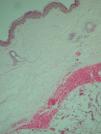

El estudio histopatológico de una de las lesiones mostraba una acumulación de tejido adiposo encapsulado, sin un aumento significativo del número de mitosis ni atipias citológicas. El componente vascular era importante, con capilares de paredes finas, hematíes extravasados y trombos de fibrina (fig. 2). El diagnóstico fue angiolipoma.

Figura 2. Tumor de tejido adiposo, encapsulado, con un aumento del componente vascular. Se observan capilares de paredes finas, con hematíes extravasados y trombos de fibrina. (Hematoxilina-eosina, ×40).